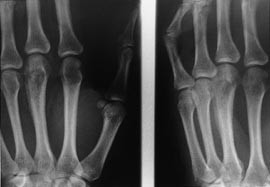

Røntgenundersøgelse af venstre hånd viste en patologisk knoglestruktur svarende til 3. metacarp med periosteal reaktion, hvilket gav mistanke om ostitforandring (fig 1). Patienten er sendt hjem til ambulant kontrol om en uge men dagen inden ambulant kontrol kom patienten i skadestuen med tiltagende hævelse, smerter og spontan perforation med pus. Sænkningsreaktion og leukocyttal var normale. Thoraxrøntgen viste ingen tegn på frisk eller tidligere lungetuberkulose. Ved revision af abscessen havde 3. metacarp ostit- og ikke maligntudseende. Postoperativt var patienten sat i behandling med dicloxacillin kapsler et gram tre gange dagligt i 14 dage og daglig skiftning ved hjemmesygeplejerske.

Røntgenundersøgelse kan vise bløddelsskygge med eller uden forkalkninger, ledansamling og senere ledkammerindsnævring, periartikulær osteopeni, periosteal reaktion, lyticlæsion eller spina ventosa (et karakteristisk fund hos børnene, hvor der er tubulær ekspansion af metacarpskaft) (6, 7).